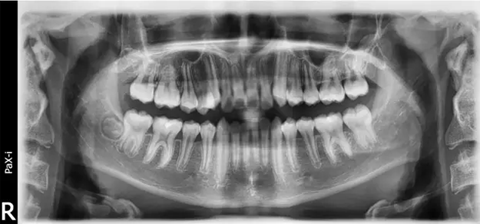

(曲面斷層片)

診斷

1)安氏Ⅲ類錯(cuò)牙合

2)左側(cè)前牙反牙合

3)前牙區(qū)擁擠,個(gè)別牙扭轉(zhuǎn)

4)上頜中線右偏